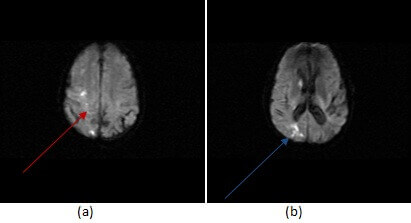

Figure 1: DWI imaging shows restricted diffusion in a watershed distribution between anterior and middle cerebral artery territories (a,red arrow) and between the ACA, MCA and PCA territories in the parietal lobe (b, blue arrow).

Diagnosis: Watershed infarct